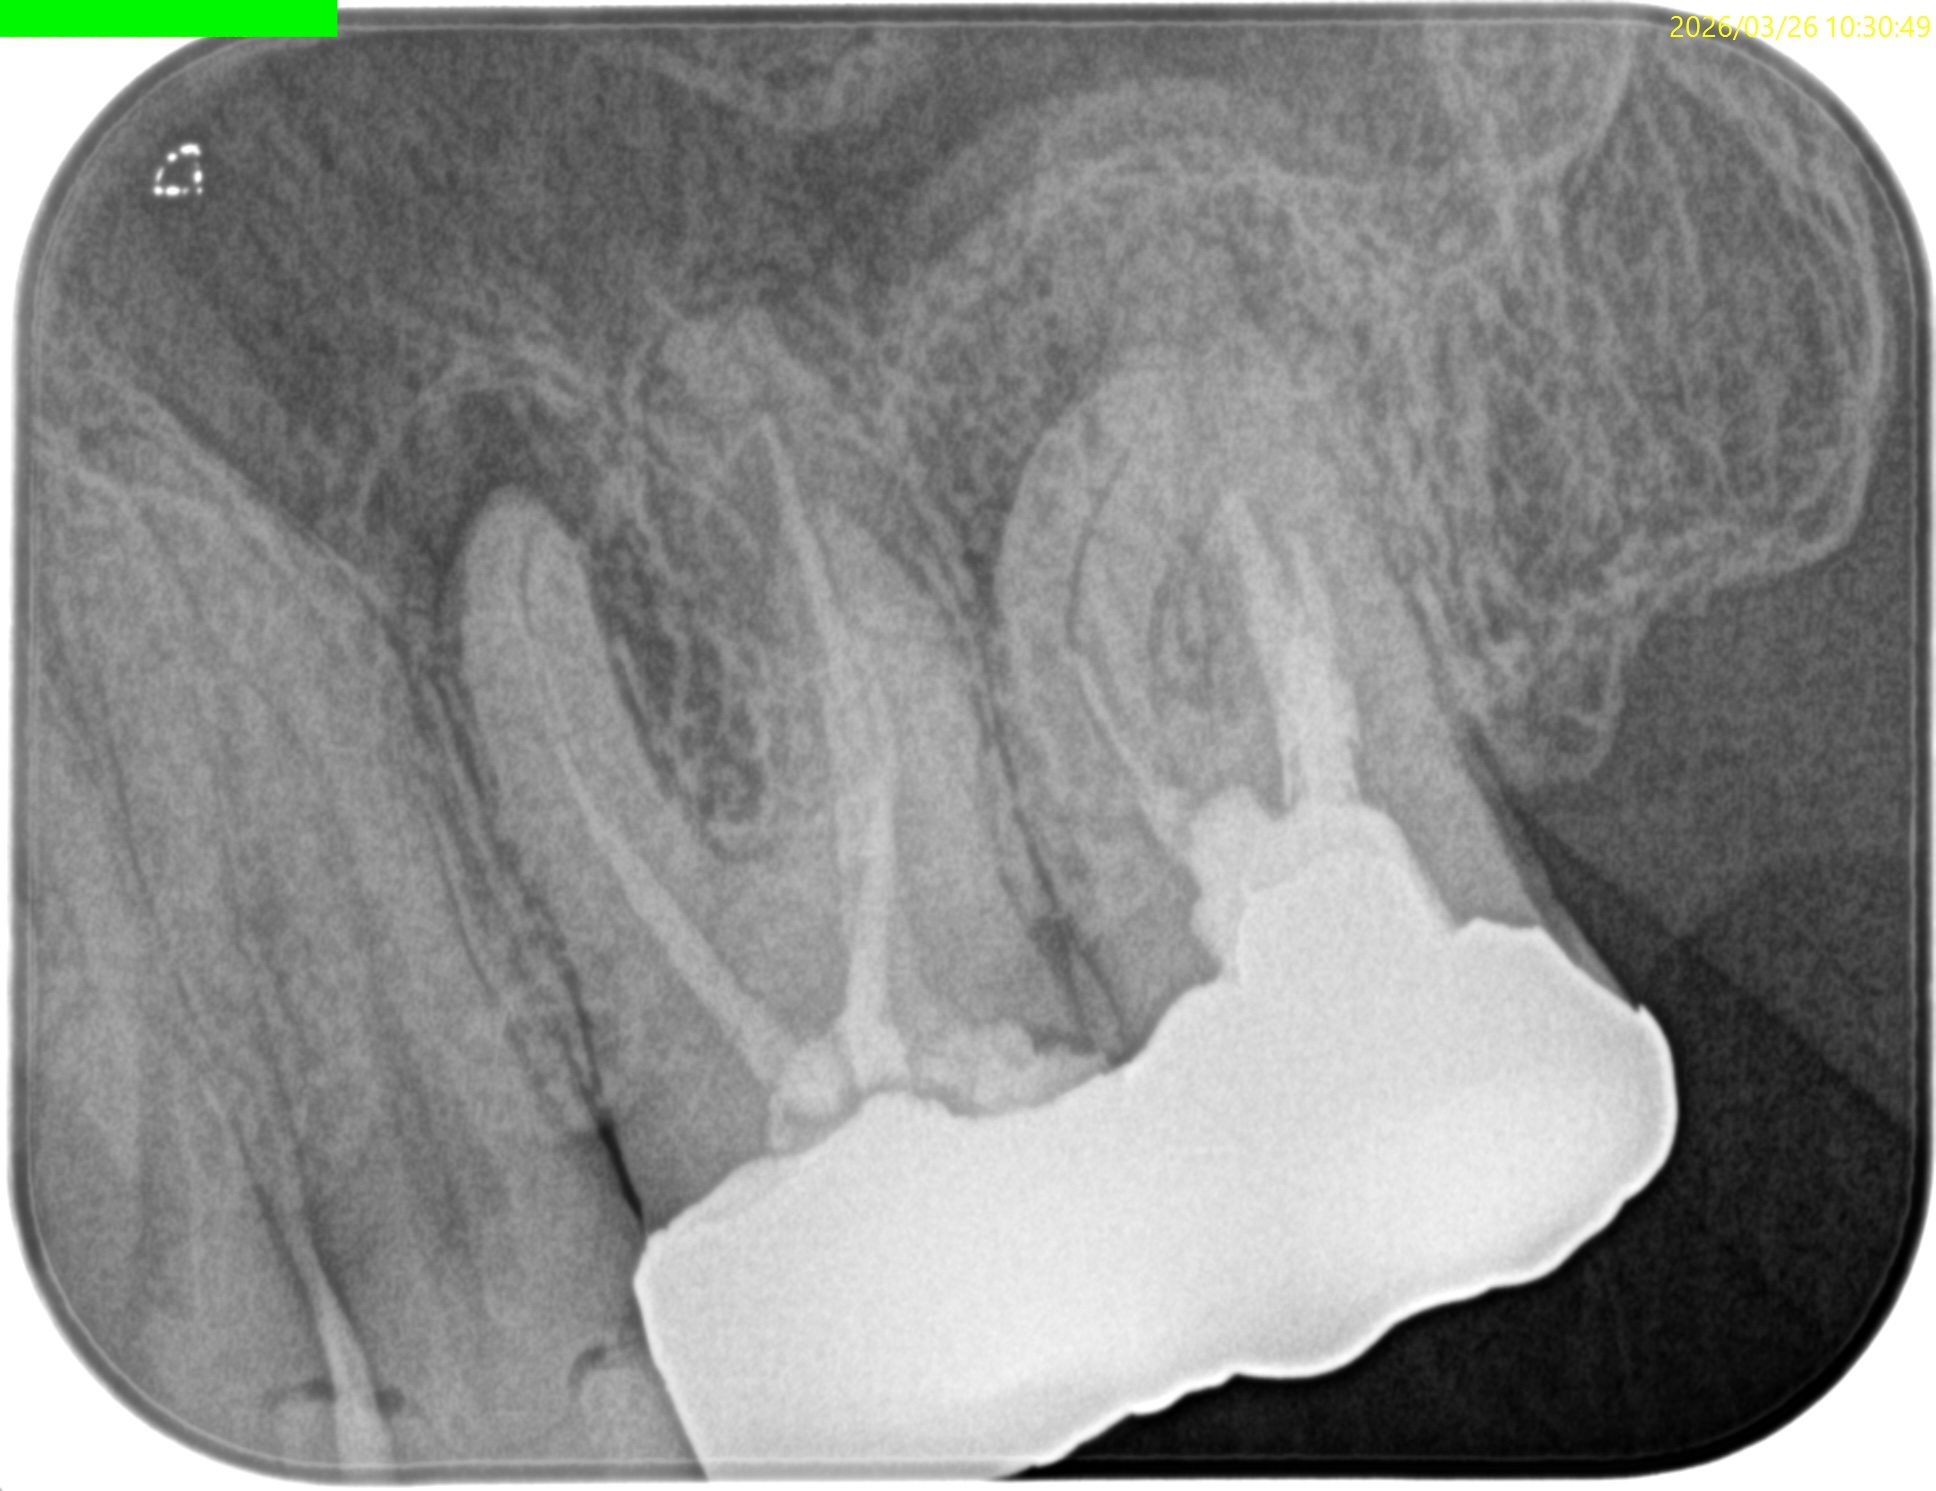

またMB2の多くはMB1と合流するという臨床的事実から形成済みのMB1に当該Gutta Percha Pointを挿入しMB2にFileを入れてグリグリとやってみた。

すると…

13.5mmの地点に傷がついていることがわかる。

ここが合流地点だろう。

これで以下のように作業を行った。

MB2は狭窄根管だがMB1と合流しているので13.5mmとして形成した。

術後のPA, CBCTは以下である。

MB1

MB2

DB

P

問題はないだろう。